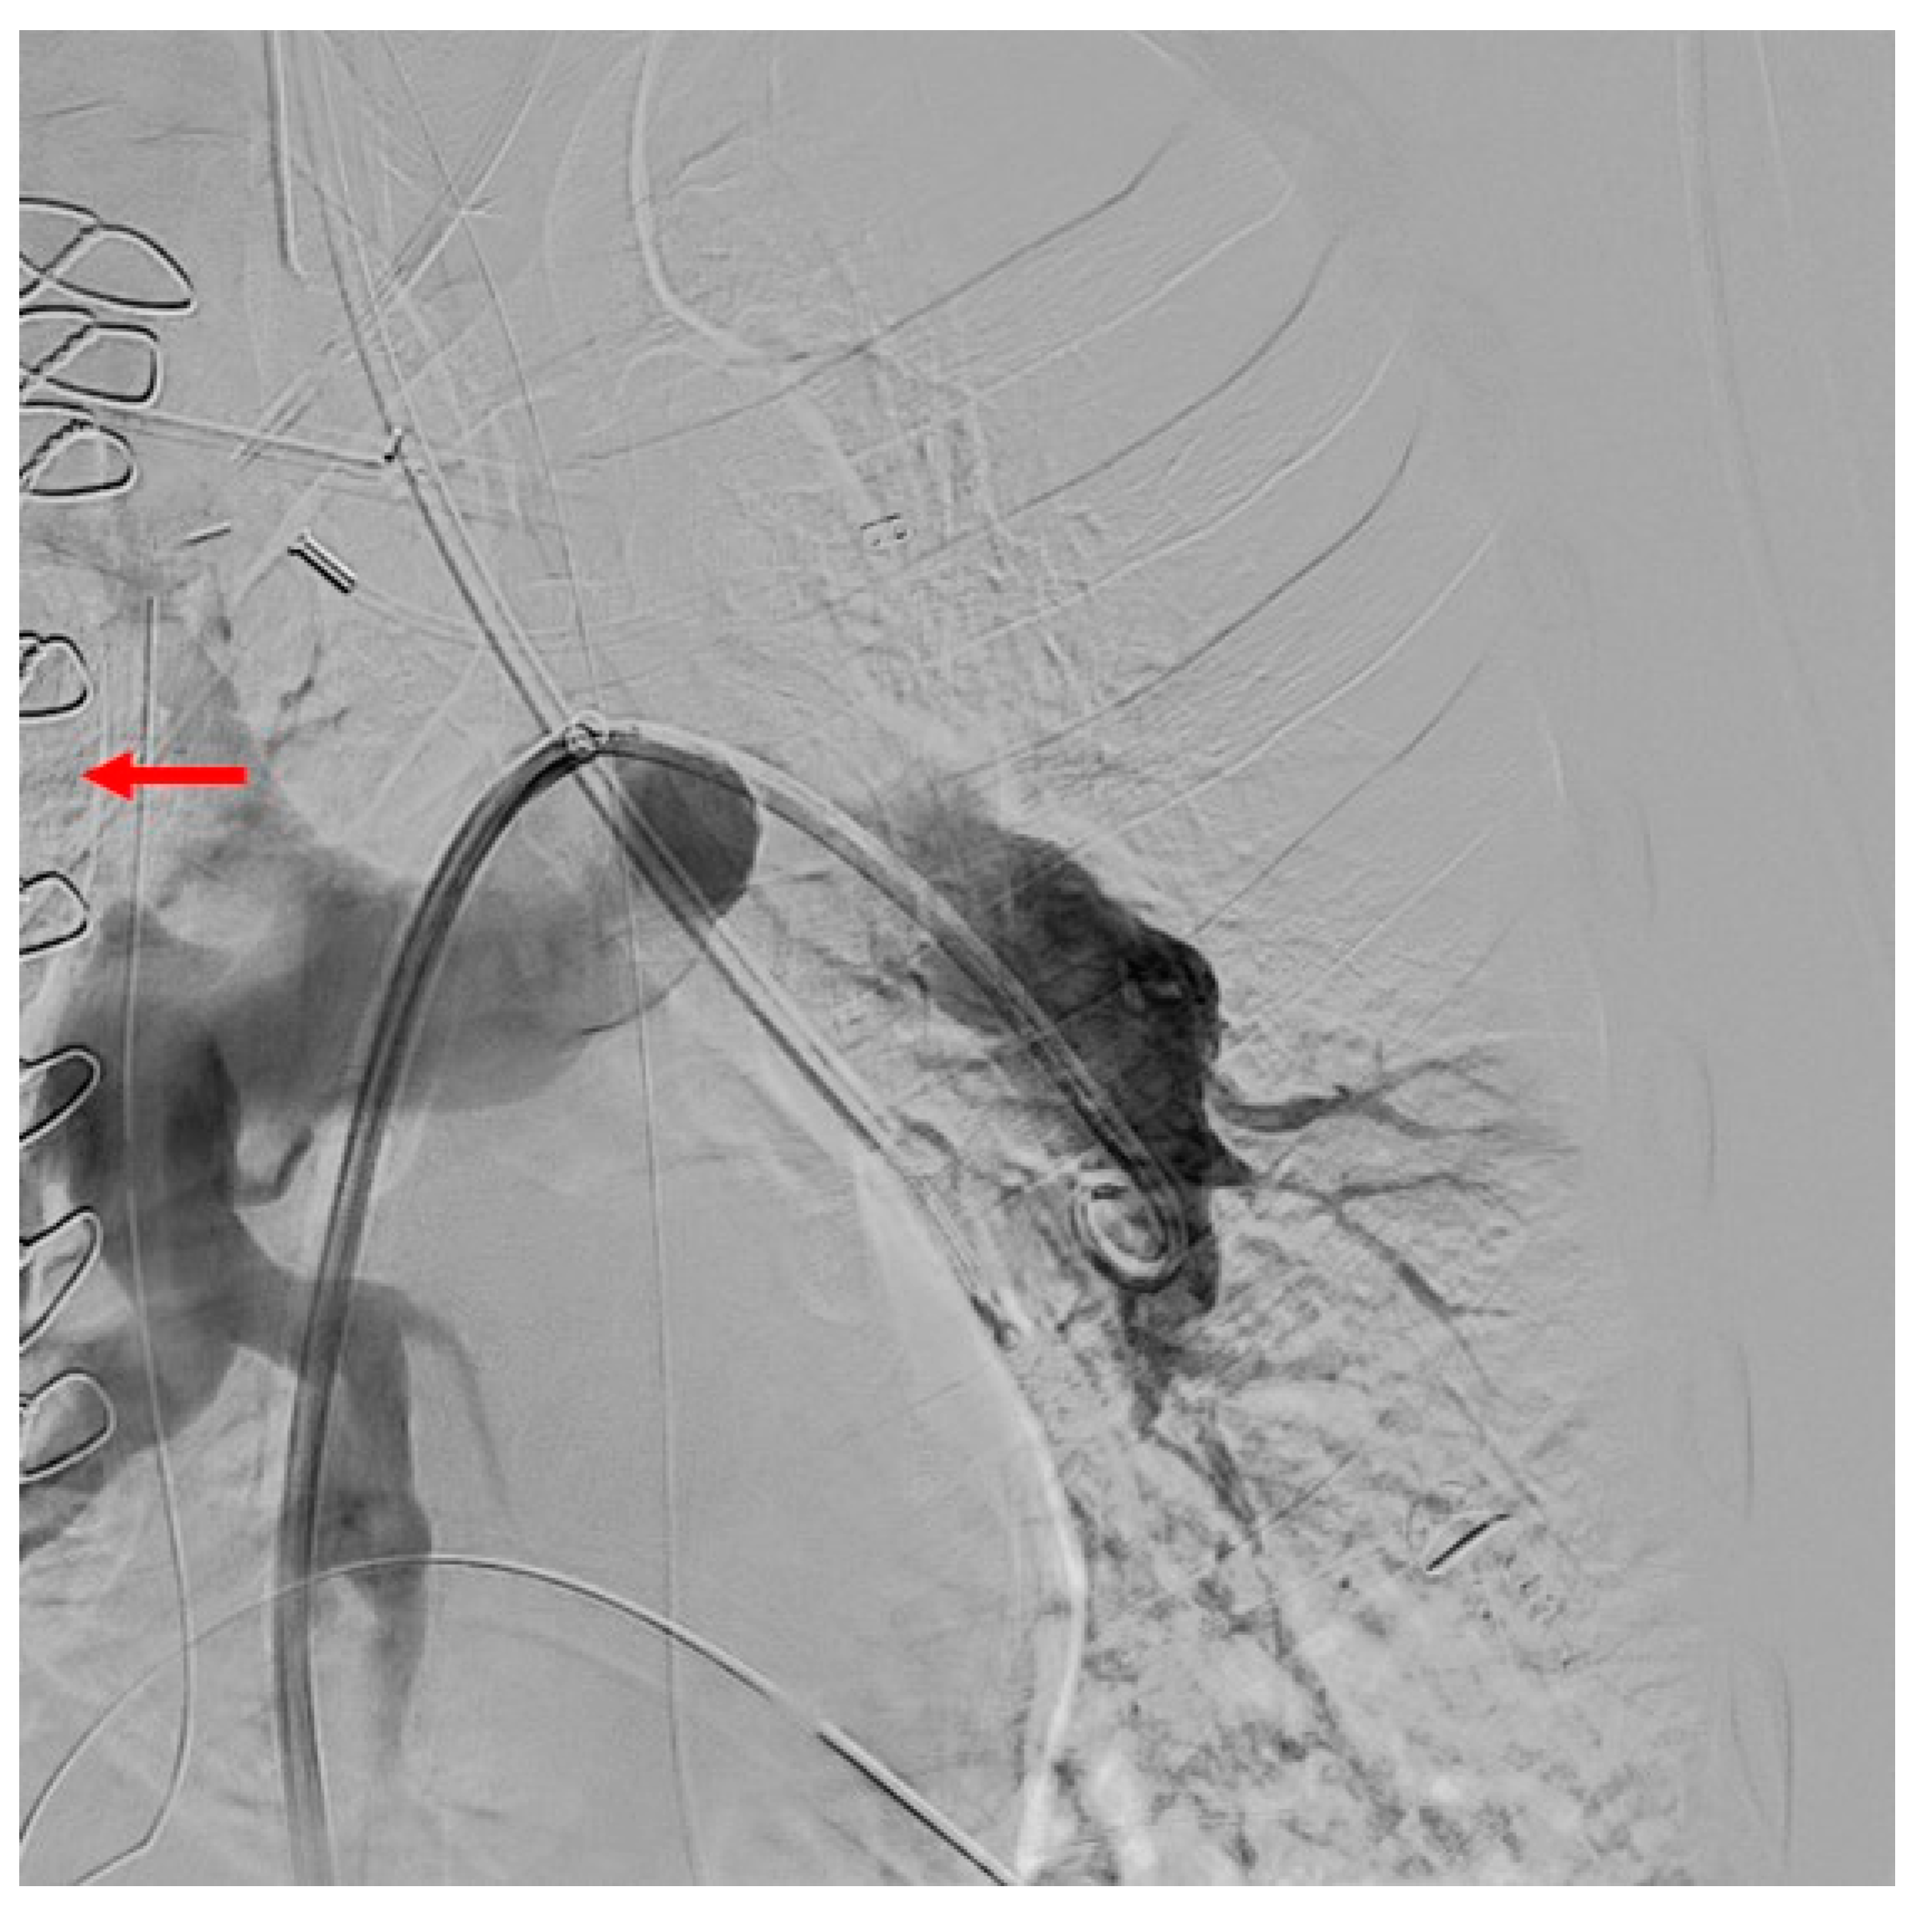

2.1. Case 1

2.2. Case 2

2.3. Case 3

2.4. Case 4